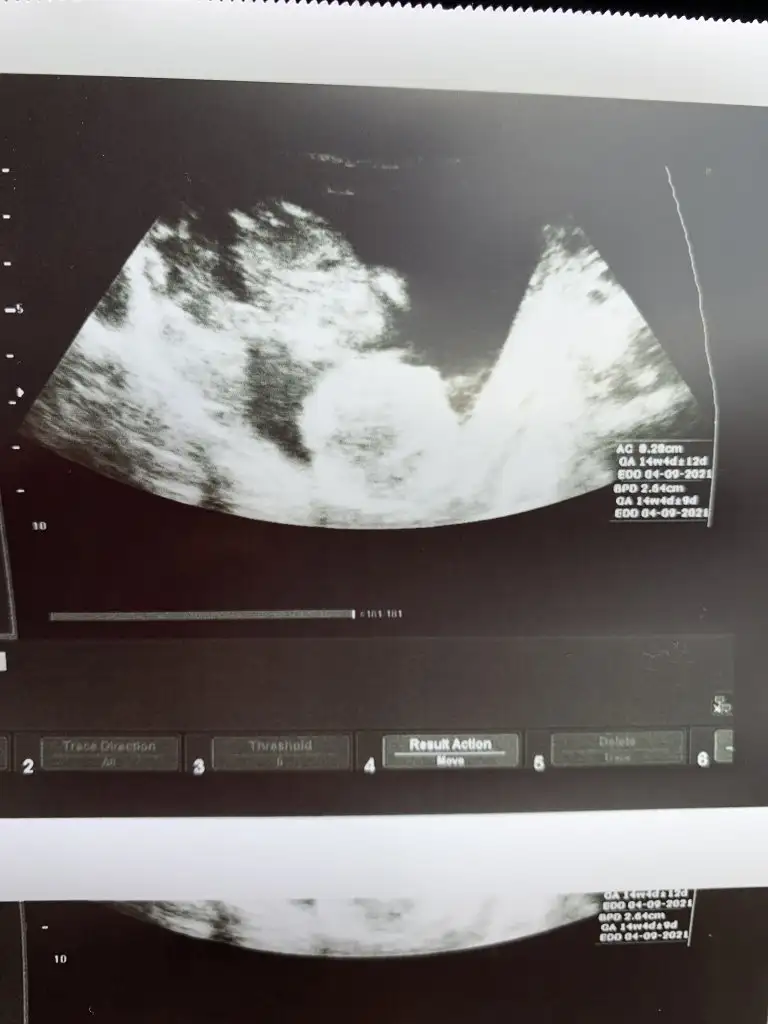

Merhaba kizlar,

Bugun de cinsiyeti ogrenemedik, gostermedi yine bacaklar falan ust uste amuda kalkmis dedi doktor

Gelisimi guzel haftasiyla uyumlu dedi doktorum. Haftaya falan tekrar bakilacak.

Eklentiler

• C04C8BC1-FE7A-4F64-BB58-8CE278E78D96.webp

24,5 KB · Görüntüleme: 87